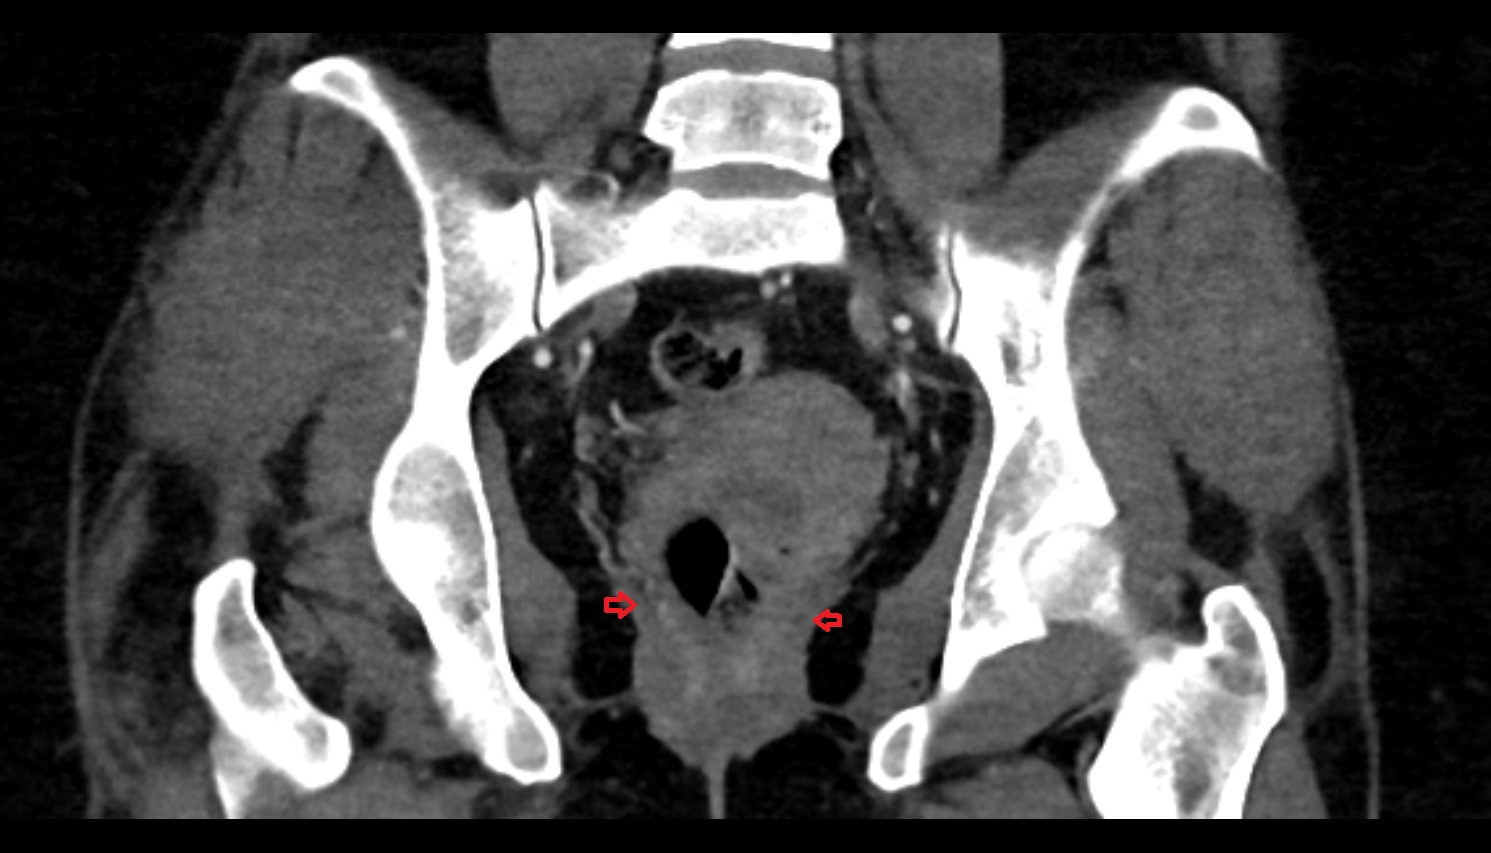

- Acetabular margin (Acetabular rim)

- Acetabulum

- Head of femur

- Neck of femur

- Hip joint

- Peripheral zone of prostate

- Transitional zone of prostate